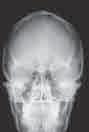

апарати у нуклеарној медицини, рендген, ултразвук, ласер, ултразвучни скенер, магнетна резонанца, ЕKG – мерење електричног импулса срца, ЕЕG – мерење електричног